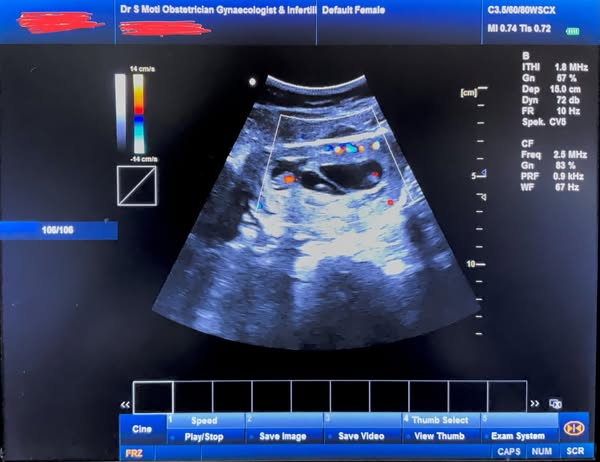

Recently, I worked with a wonderful couple on their path to parenthood. Through careful monitoring and support, we were able to achieve a successful IUI. However, during a routine ultrasound, a delightful surprise awaited us – four tiny heartbeats! While surprised, the couple was overwhelmed with joy at the prospect of quadruplets, along with a touch of apprehension.

Disclaimer: This is for informational purposes only and should not be taken as medical advice. Some areas on my ultrasound pictures have been struck off due to privacy. Pls do not ask any questions related to this specific post. Thank you for understanding.